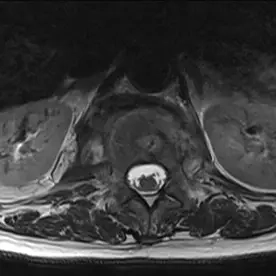

In der angefertigten MRT des LWS und des Abdomens zeigt sich eine kräftige T2w-Signalanhebung in den Wirbelkörpern BWK 12 und LWK 1 mit Irregularitäten der Abschlussplatten (Bild 1). Die angrenzende Psoasmuskulatur zeigt sich auch signalalteriert, betont auf der rechten Seite (Bild 2). Bei der Kontrastmittel-Unterstützer-Untersuchung zeigt sich ein kräftiges Enhancement in den Wirbelkörpern und der angrenzenden Muskulatur (Bild 3). Besonders auf der rechten Seite zeigen sich zudem auch abszessartige Formationen (Bild 4).

Der Befund ist vereinbar mit einer Spondylodiszitis von BWK 12/LWK 1 mit Absenkung in den Musculus psoas beidseits, rechtsbetont, differentialdiagnostisch ist hier an eine Tuberkulose als Ursache zu denken.